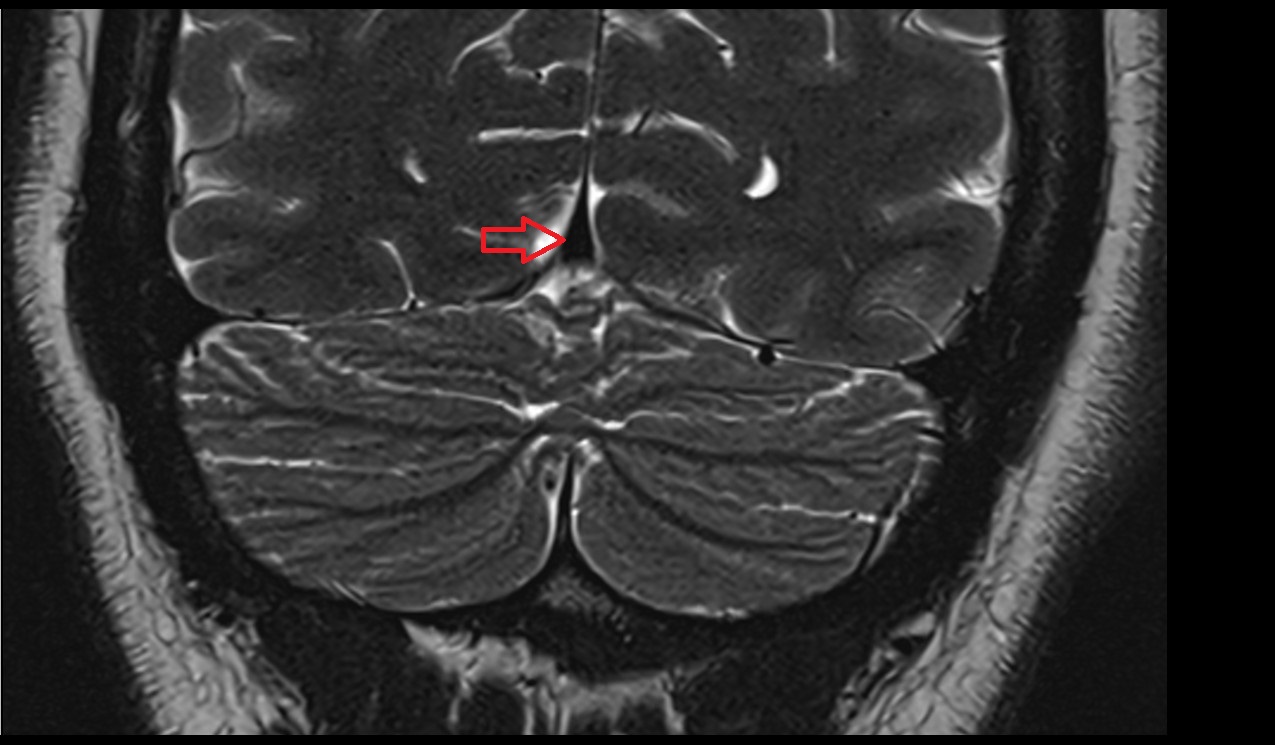

- Median aperture of fourth ventricle (foramen of Magendie)